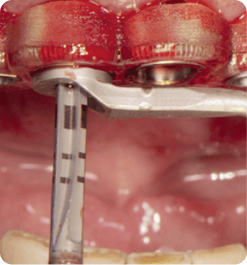

IMERSÃO EM CIRURGIA GUIADA

Coordenação: Paulo Abdalla Saad

• Teórico

• Prático

• Demostrativo